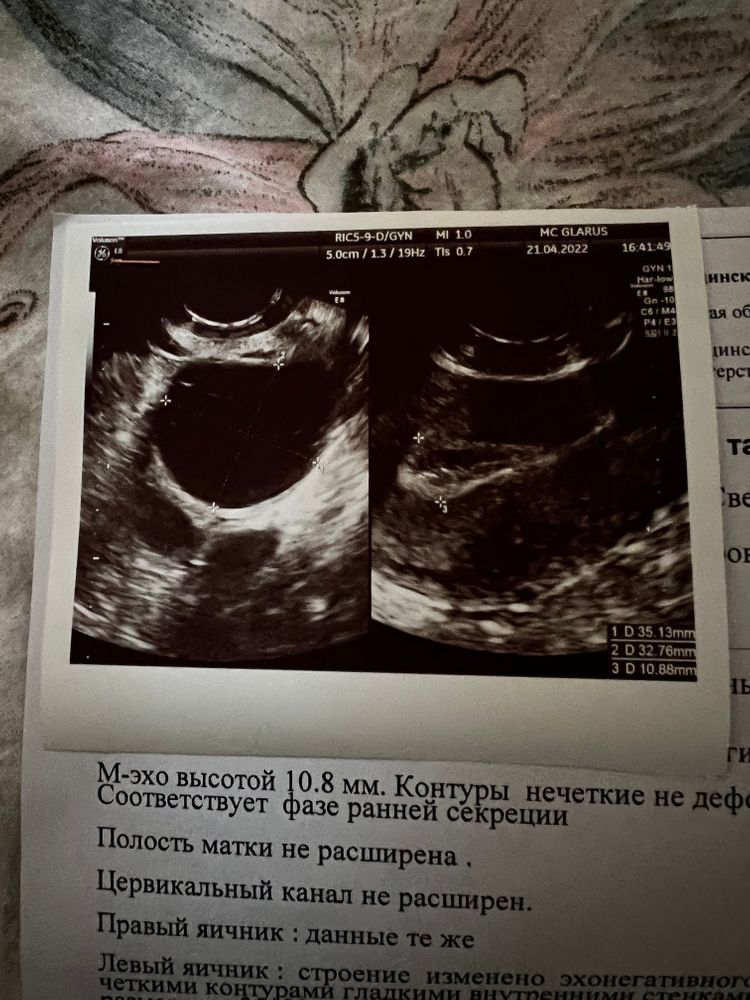

Сегодня 21 ДЦ, стимуляция овуляции. На узи картина кисты желтого тела. Переживаю может ли наступить беременность при такой картине.

21 ДЦ, узи